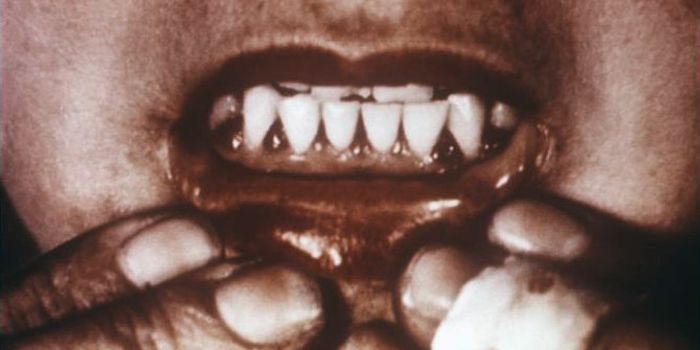

AUG 07, 2022MicrobiologyPolio is a disease caused by the poliovirus. Polio can cause flu-like symptoms like nausea, headache, fever, and sore th ...